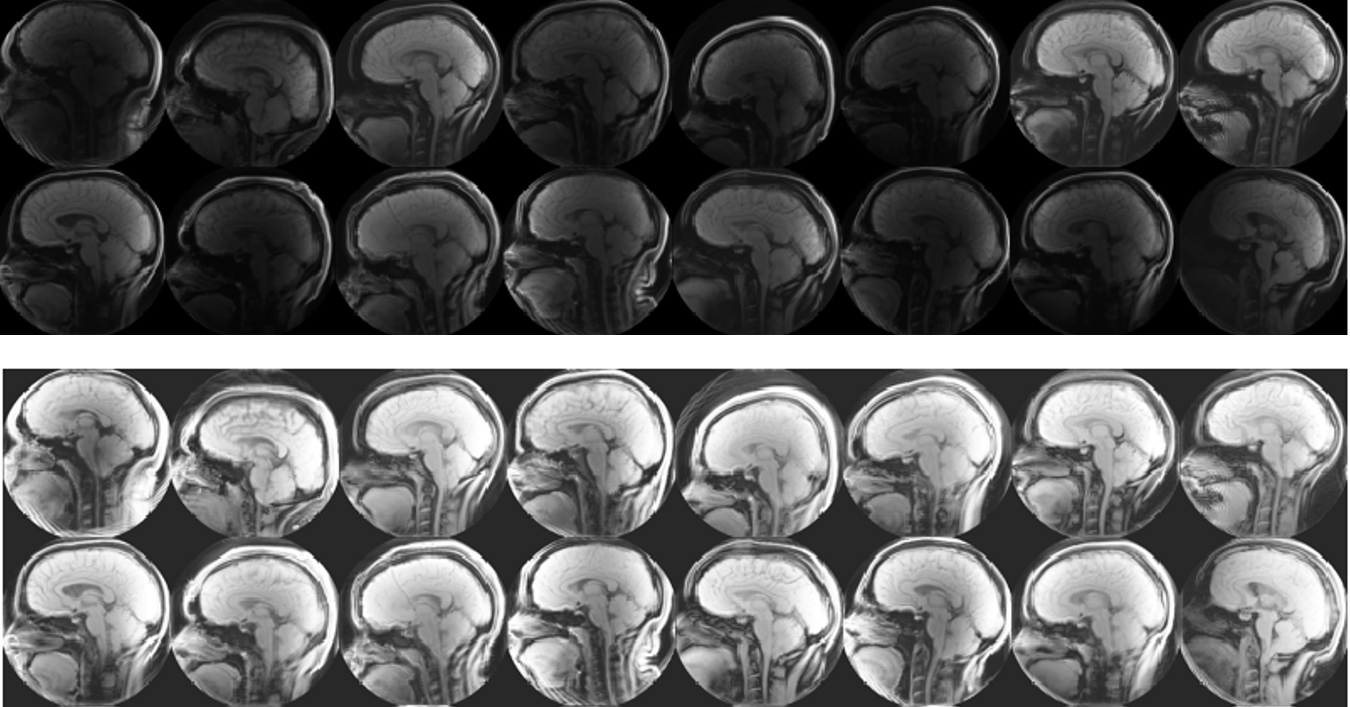

Chiari malformation is a condition in which brain tissue extends into the spinal canal. While it can be difficult to diagnose Chari from anatomical images, a promising new direction for diagnosis is by looking at brain movement . Using an MRI technique called DENSE (shown below) that records how the brain moves, Dr. Oshinsky’s group (at Emory’s Dept. of Radiology) collected data about how Chiari patients have more brain movement in the cerebellum and brainstem than controls.

This method may be more accurate in diagnosing Chiari, however, the large number of manual processing steps may limit its use as a wide-spread screening tool. This project aims at exploring the use of machine learning algorithms to automize parts of the image processing pipeline, most critically the segmentation of the image into different brain regions. The teams worked with image data that has been collected and labeled by Dr. Oshinski’s group in a previous research study. The project is accessible to the team members since we can build upon recent progress and software made in image processing and computer vision and the image data is two-dimensional and of limited resolution, which enables fast experimentation. Despite this simplicity, the project allows us to investigate ML in a realistic setting and investigate the generalization properties and robustness of the approach.

Week 2: One of the first things we noticed when we began working with our data set the first week was the variability in the brightness and contrast of our images. In week two, we explored some different methods to help enhance the images. We decided to use a tool in MATLAB’s Image Processing Toolbox to normalize the images in a process called histogram normalization, which made our images much more consistent.